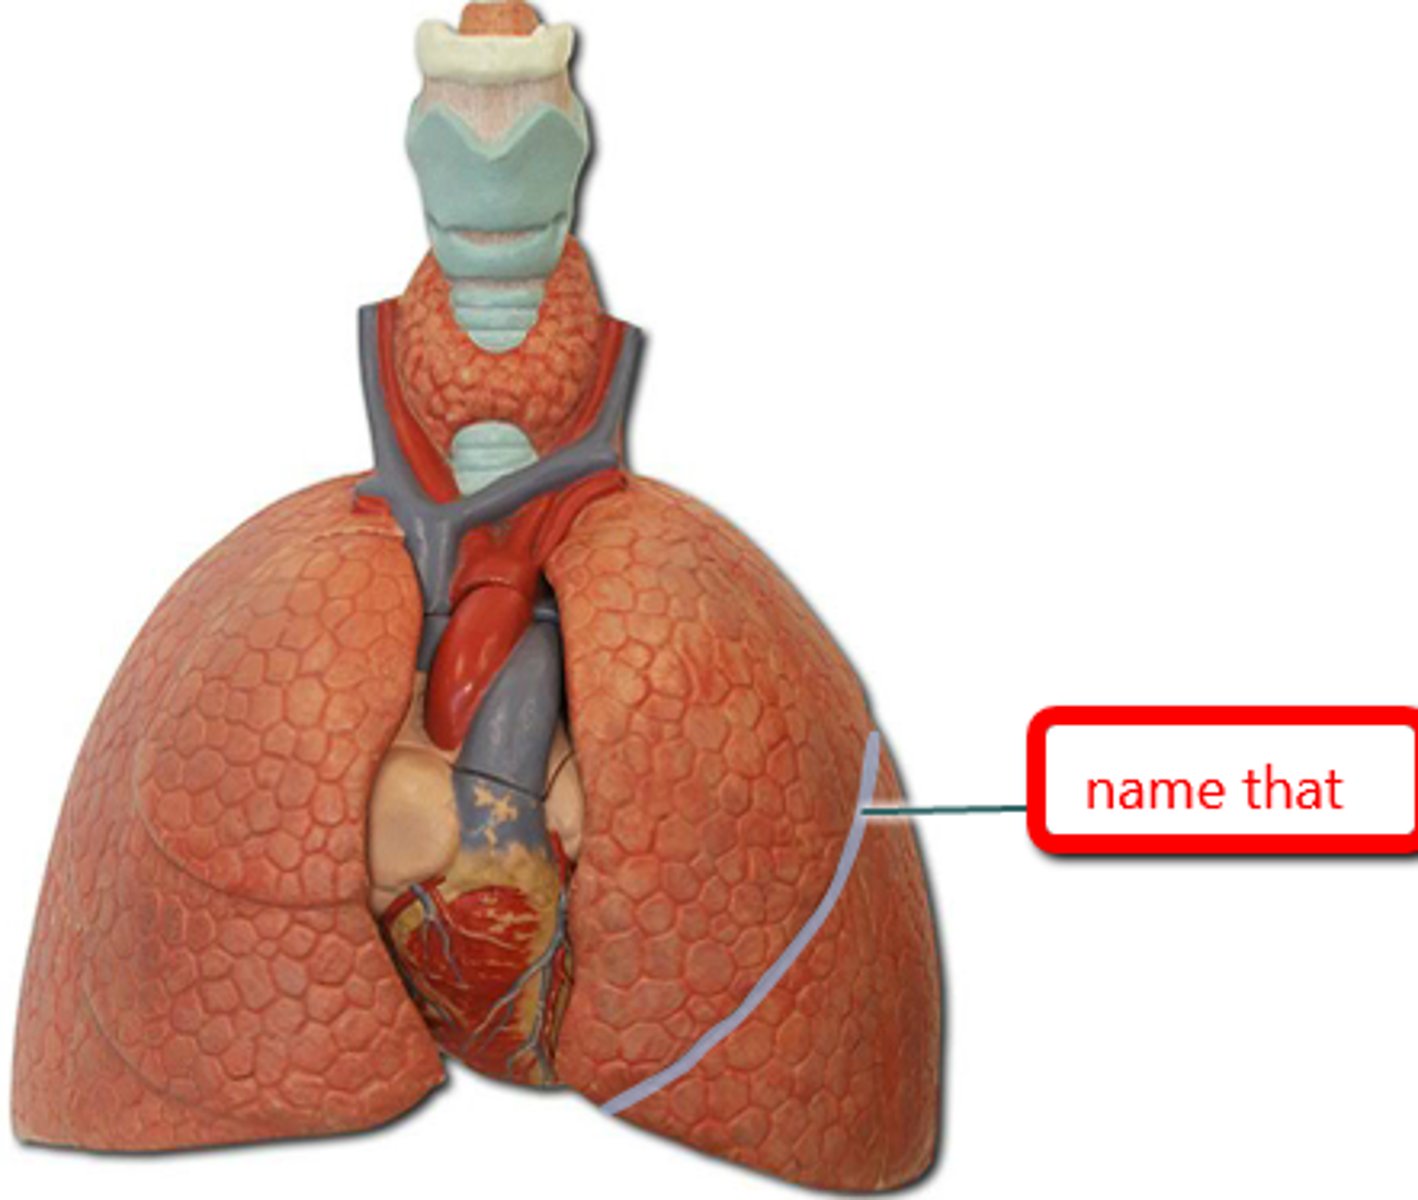

lingula

a tongue-like extension of the left superior lobe projects anteriorly over the heart

cardiac notch

a concave space on the left lung in which the heart lies